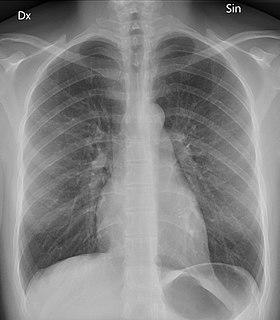

A normal posteroanterior (PA) chest radiograph of someone with Interstitial Pneumonia. Dx and Sin stand for "right" and "left" respectively. | |

A chest radiograph, called a chest X-ray (CXR), or chest film, is a projection radiograph of the chest used to diagnose conditions affecting the chest, its contents, and nearby structures. Chest radiographs are the most common film taken in medicine.